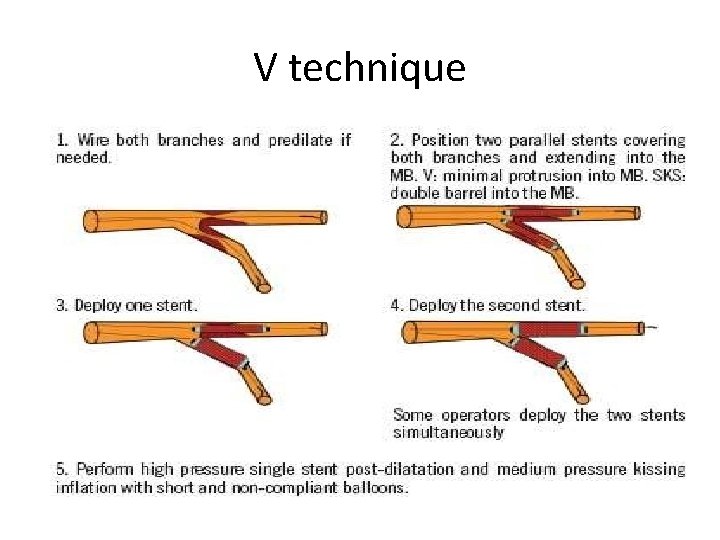

Stenting techniques 1)Provisional • Mainvessel stenting ± side branchangioplasty (Provisional) Tstenting, • TAP, • REVERSEINTERNAL CRUSH • REVERSECULOTTE. 2) elective • Culotte-stenting • Crush technique (reversecrush) T TECHNIQUE AND TAP • V STENTING • Y STENTING(SKS technique)

V technique